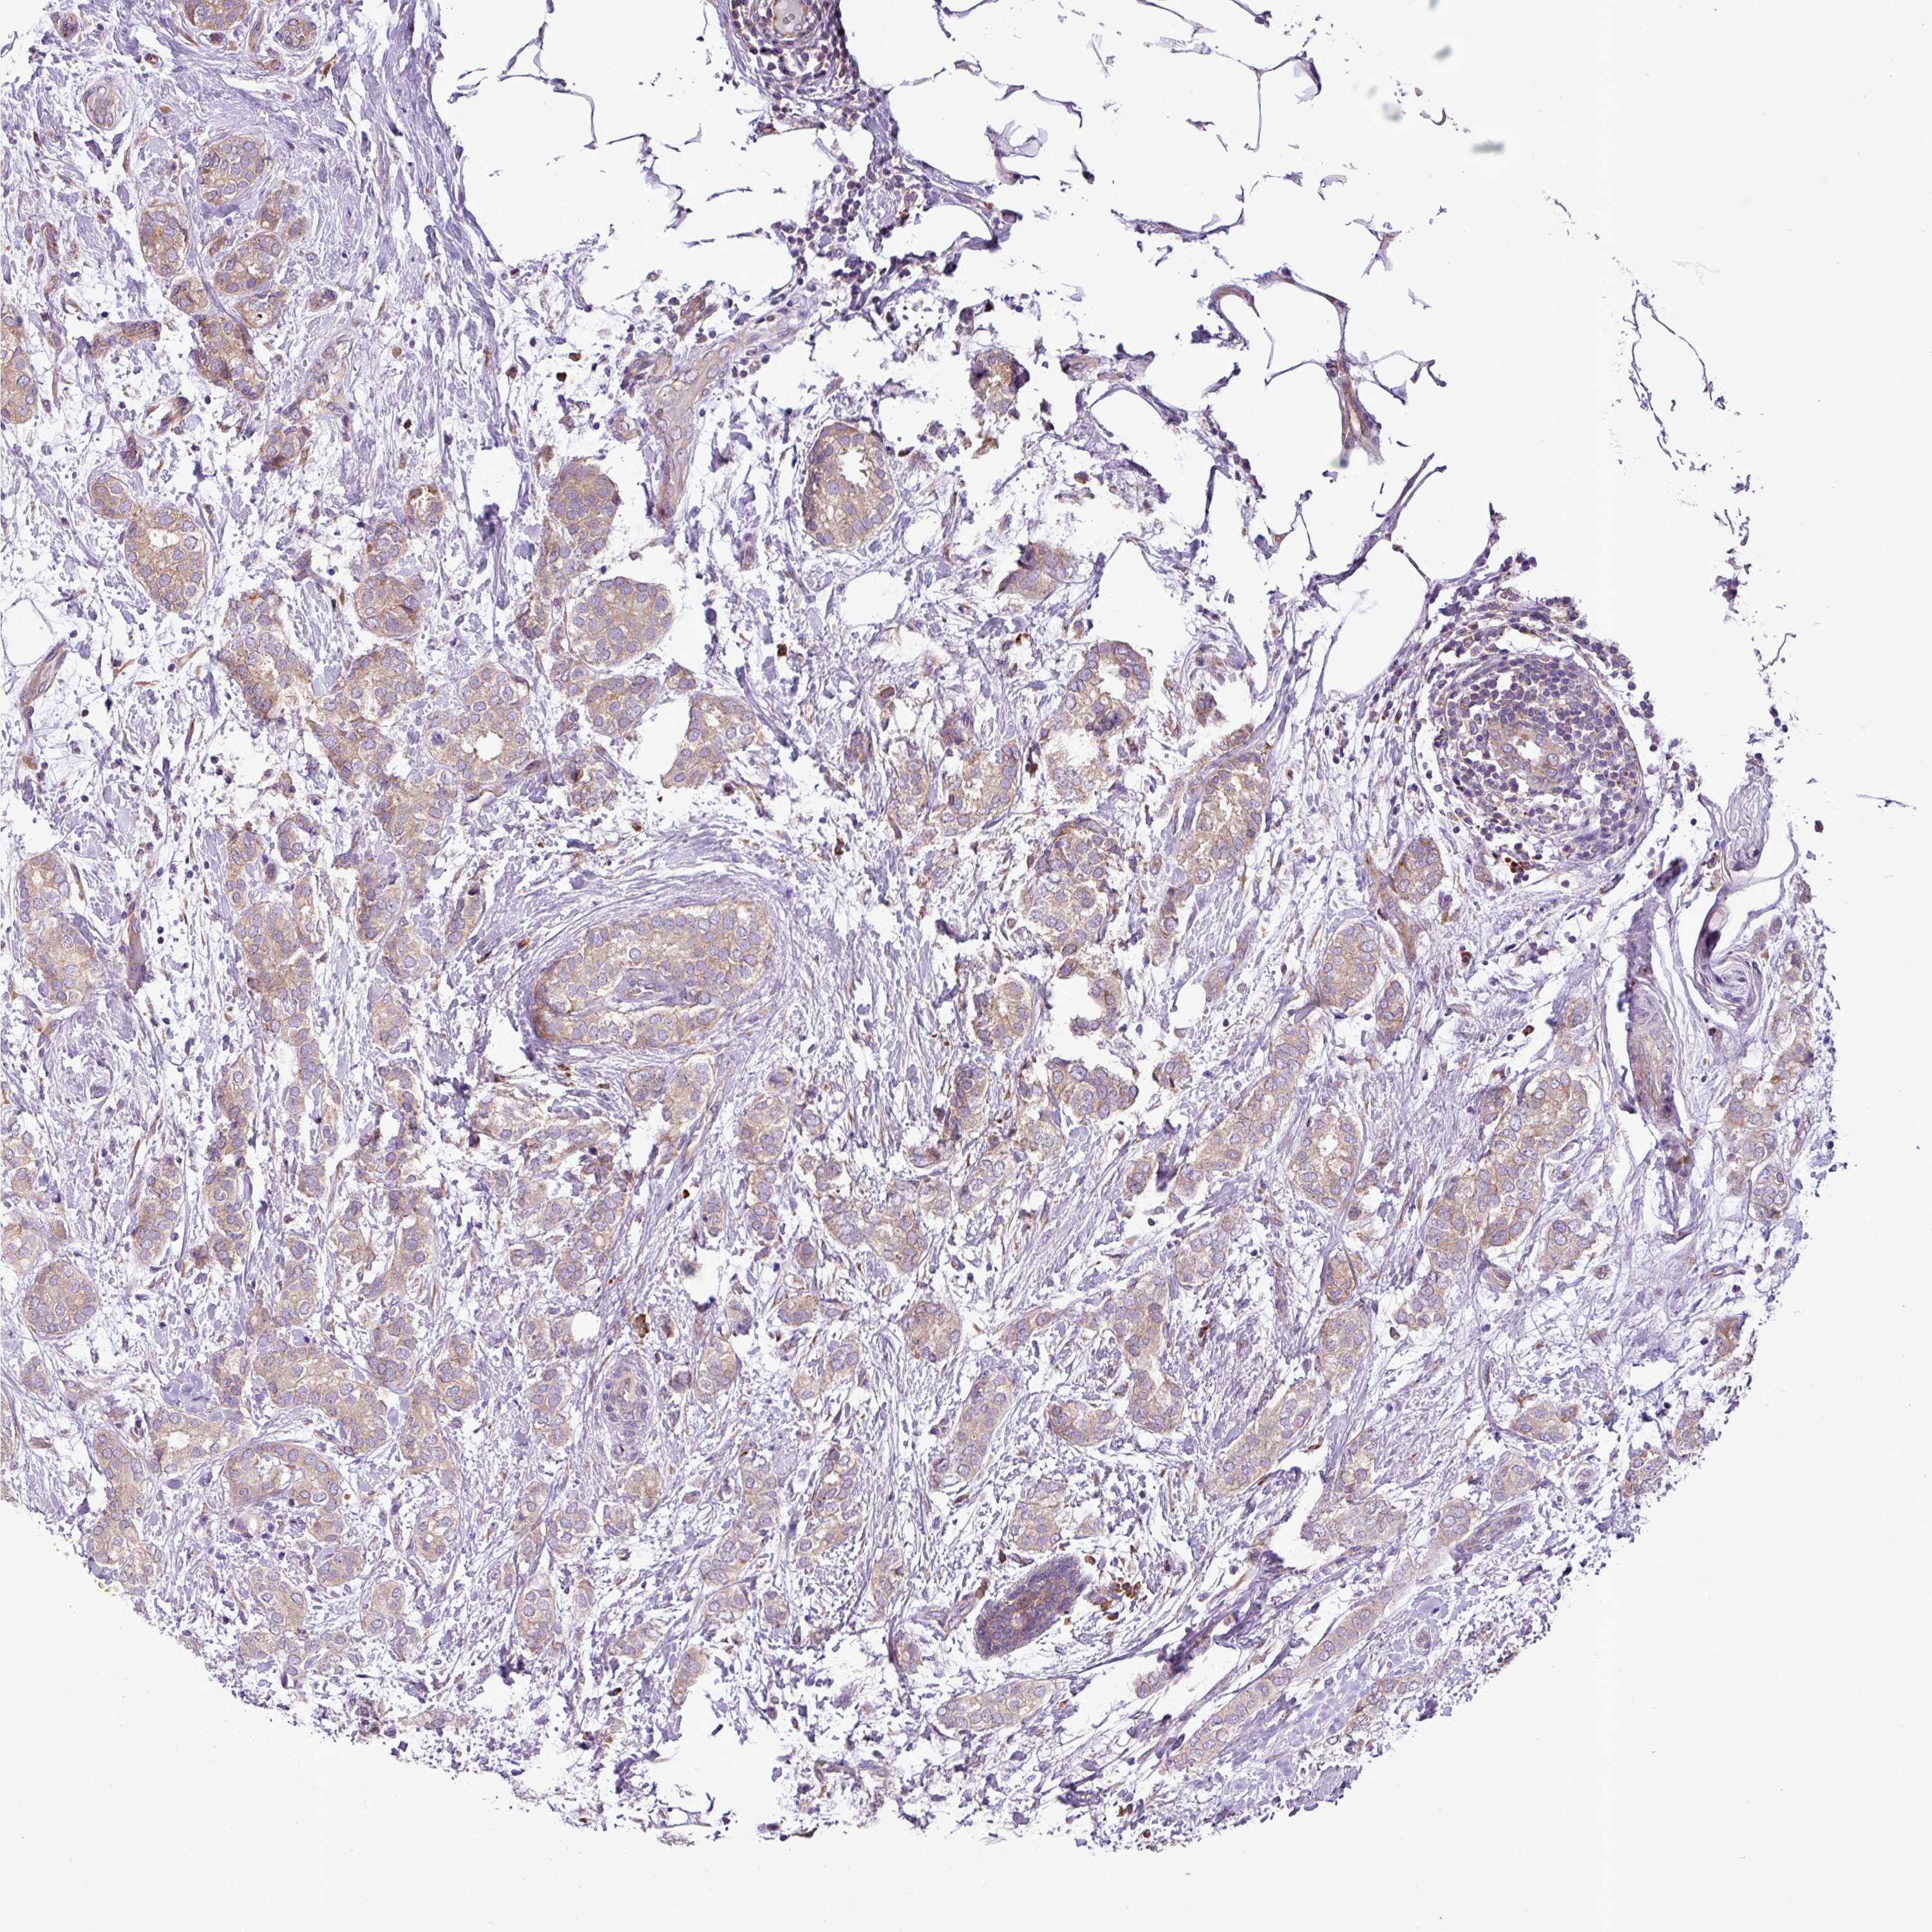

CANCER BREAST CANCER Show tissue menu

BRCA TCGA BRCA VALIDATION PROTEIN EXPRESSION